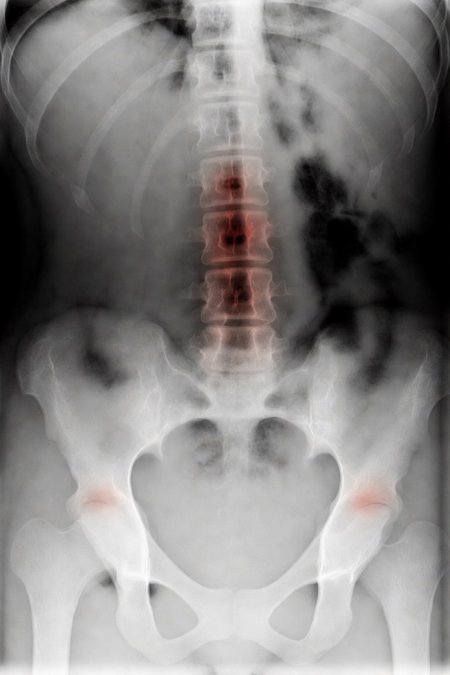

Can a model like Flux Kontext, designed for editing art and photography, be used to work with medical images, for example, with something 'as simple' as red-marking fractures?

The quick answer: it does do something interesting, but it over-scores and is far from reliable as a medical tool. It's a prototype to play with the idea, nothing more.

2. Ask: “Make marks where there is a fracture”.

Test results:

False positives ≈ 24%

Fracture detection ≈ 20%

Sensitive mode (more detection, lots of noise)

Euler, 15 steps, Karras

Denoise 1.0

Result:

False positives ≈ 80%

Fracture detection ≈ 86%

Even more aggressive settings (e.g. rk beta57 to denoise 1.0) reach the absurd: 100% false positives and 100% detection: it paints everything red and almost hits all fractures beyond marking healthy areas, for an untrained eye.